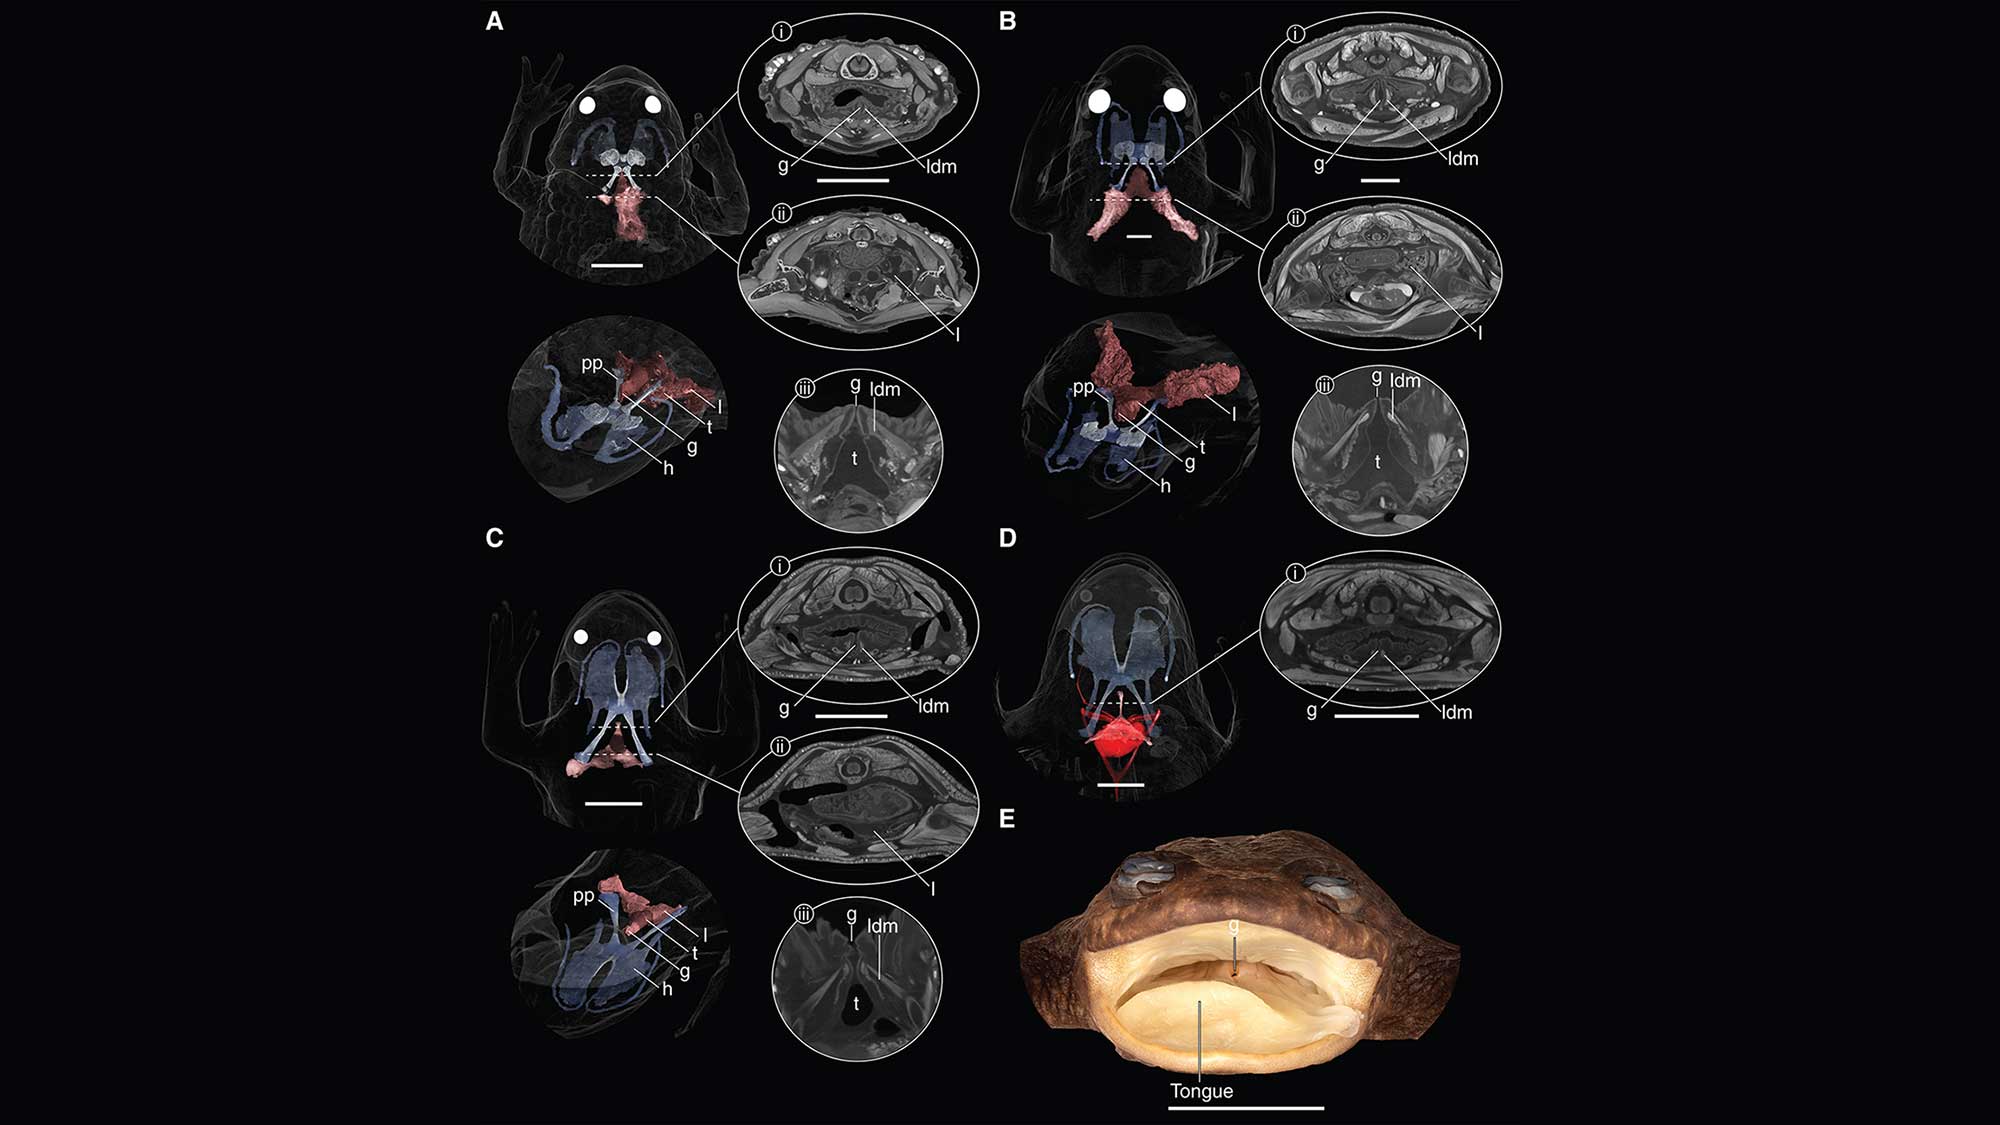

History document tiny lungs in a 'lungless' frog using a high-resolution CT scanner. David C. Blackburn, Jaimi A. Gray, Edward L. Stanley

The new study, however, employed a high-resolution CT scanner; the newer tech enabled researchers to identify lungs in two iodine-soaked specimens that had been collected and examined by the previous study’s authors.

If this frog species’ lungs were inflated, they’d be “substantially smaller than your pinky fingernail,” said Blackburn. The lungs of this particular species appear to be far smaller “than the most closely related species that lives on the Philippines island of Palawan,” the biologist added.